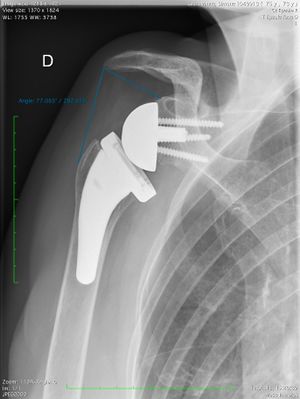

Acute proximal humerus fracture Reverse shoulder arthroplasty is a more reliable treatment than hemiarthroplasty for complex proximal humerus fractures at least in elderly patients because its functional outcomes appear to depend less on tuberosity healing and rotator cuff integrity (Figure). Lädermann

Figure : Reverse shoulder athroplasty for fracture

Figure: A) Anteroposterior radiograph of a proximal humerus fracture; B) post-operative radiograph of the fracture treated with reverse shoulder arthroplasty.{Lädermann, 2019 #4454} Pklease refer to fracture chapter